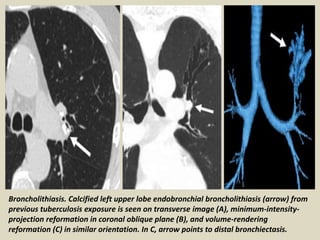

Broncholithiasis Calcified or ossified material within

the bronchial lumen can cause focal bronchiectasis.

By far the most common cause of broncholithiasis is

erosion by and extrusion of a calcified adjacent lymph

node, usually associated with a long-standing focus of

necrotizing granulomatous lymphadenitis, especially

after tuberculosis. Nevertheless, the frequency of

broncholithiasis complicating granulomatous

infection is quite low. The most common sites are the

proximal right middle lobe bronchus and the origin of

the anterior segmental bronchus of the upper lobes

because of airway anatomy and lymph node

distribution.

Broncholithiasis. Calcified left upper lobe endobronchial broncholithiasis (arrow) from

previous tuberculosis exposure is seen on transverse image (A), minimum-intensity-

projection reformation in coronal oblique plane (B), and volume-rendering

reformation (C) in similar orientation. In C, arrow points to distal bronchiectasis.